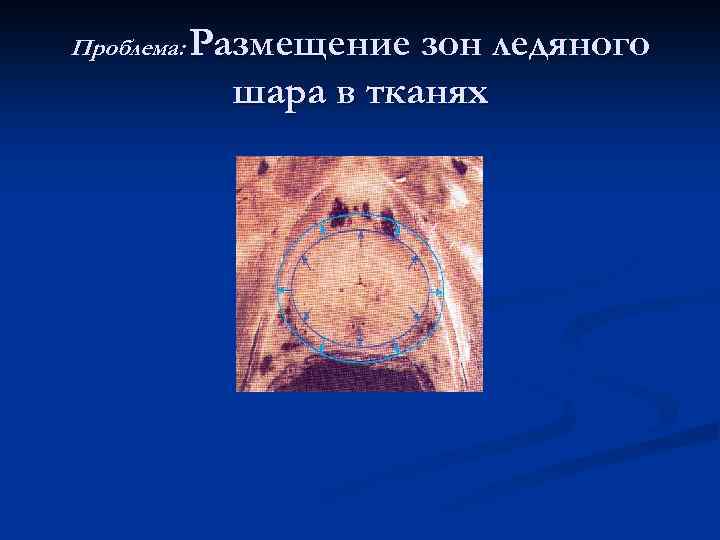

Проблема: Размещение зон ледяного шара в тканях

Проблема: Размещение зон ледяного шара в тканях